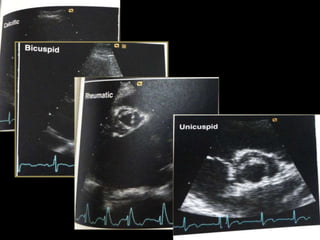

Bicuspid Aortic valve

Bicuspid Aortic Valve (BAV)

 Accounts for 2/3rd of cases of severe AS in adults < 70 yrs.

 1/3rd of cases in adults > 70 yrs of age.

 Severe AS of a BAV is difficult to be differentiated from that of tricuspid

one.

 Usual view for differentiation is PARASTERNAL SHORT AXIS VIEW at

the level of great vessels in systole.

 PARASTERNAL Long axis view shows systolic bowing of the leaflets into

aorta – “Dome like”.

 M MODE – Eccentric closure line (to be taken at the tips of bowed

leaflets).

 Two cusps are seen in systole with only two commissures framing an

elliptical systolic orifice (the fish mouth appearance).

 Diastolic images may mimic a tricuspid valve when a raphe is

present.

Unicuspid aortic valve

 Single eccentric orifice

 Prominent systolic doming

 Acommisural

 unicommisural

Rheumatic Aortic Stenosis

 Characterized by

 Commissural fusion

 Triangular systolic orifice

 Thickening & calcification

 Accompanied by rheumatic mitral valve changes

 Parasternal short axis view showing commissural fusion, leaflet

thickening and calcification, small triangular systolic orifice